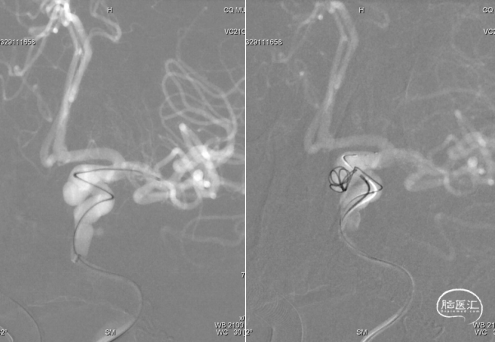

建立治疗通路后,在微导丝引导下分别将塑性好的弹簧圈微导管及支架微导管超选至左侧颈内动脉床突旁动脉瘤及左侧大脑中动脉远端;释放支架后,填入弹簧圈实现动脉瘤的致密填塞;在整个过程中Tethys®中间导引导管提供稳定支撑。

术后造影提示动脉瘤内弹簧圈致密填塞,动脉瘤不显影,瘤颈封堵可,左侧颈内动脉通畅。